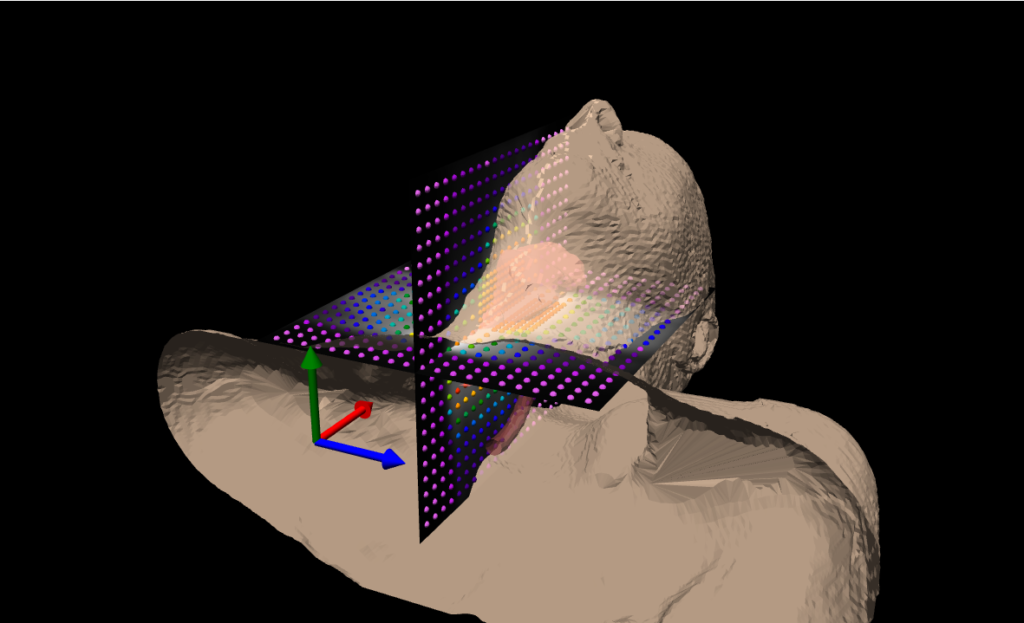

The Delta4 Phantom+ MR is an innovative device for addressing pre-treatment quality assurance (QA) for highly modulated radiotherapy treatment plans in MR-linacs.

It is the ONLY system that measures the dose distribution in the isocentric region and not simply in one single flat or wrapped plane.

The patented geometric, dual orthogonal detector planes and the nature of the detectors make the Delta4 Phantom+ MR a unique quality assurance system.

- Isocentric measurements in two orthogonal detector planes

- 1069 p-type silicon diodes

- Resolution 5 mm at isocenter, can be increased to 2.5 mm by merging

- Measures where it matters